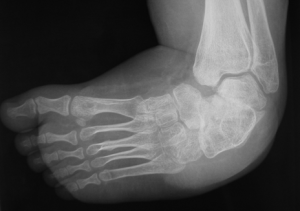

Il piede torto congenito, conosciuto anche come talipes equinovarus, è una condizione in cui il piede del neonato è rivolto verso l’interno. Si tratta di una patologia malformativa complessa, con alcune caratteristiche peculiari.

Il piede torto congenito è un’associazione di diverse deformità a carico di diversi segmenti anatomici del piede e delle diverse componenti articolari.

Esistono diverse classificazioni per definire la gravità della patologia e le deformità tipiche (equino, varo, supino).